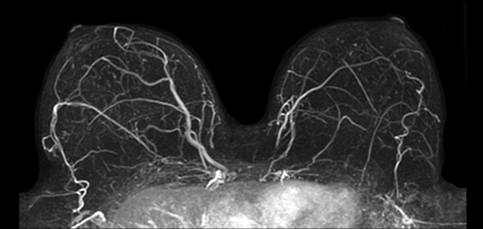

Yesterday, I finally had that MRI I’ve been waiting on for what feels like forever, but was just a couple weeks. I’d had a CT scan before (the one where you have to drink horrifying chalky liquid flavored to resemble Hell’s pina colada), but this was my first MRI. Quick note: MRI stands for Magnetic Resonance Imaging and uses a powerful magnetic field, radio frequency pulses and a computer to produce detailed pictures of your insides. In my case, my breasts. The purpose of this test was to see if there was anything hinky going on in my boobs that the mammogram didn’t pick up. Specifically, we were on the lookout for naughty lymph nodes. If Turdy the Tumor wants to conquer new ground, he’ll go for the lymph nodes first.

I lay face-down on the tray-thingie with my boobs dangling down into a hole and my face in a donut-ish pad. I made a joke to the tech that the picture probably would have been better three kids ago. She laughed, but she couldn’t be much older than 21. She’ll learn.

The tech checked in with me every once in a while through the headphones. “Doing okay, Christa?” “Yep.” My cheekbones were a little sore from being pressed into the donut. The tech warned me that she was about to inject the contrast dye into my IV and I asked if I could move my head. She said the picture would be better if I didn’t move at all. So I didn’t. The dye felt a little bit cool as it went in, but not uncomfortable.